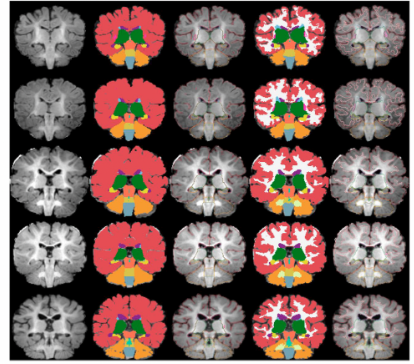

volumetric segmentation 과정 - GM/WM 분리 하지않은 데이터셋

GM/WM 분리가 되지 않은 데이터에 5가지 segment 방법

위 ↔ 아래 : 2개월/3개월/5개월/6개월/9개월

왼 ↔ 오른쪽 : 정규화 및 skullstripped T1 input 이미지 / 수동 segment / 바깥라인 수동 segment / 자동 segment / 바깥쪽 자동 segment